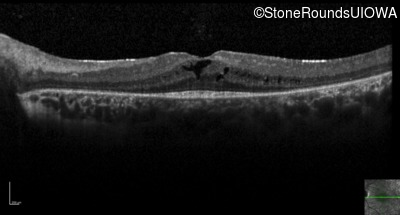

Optical Coherence Tomography - Right - 20/40

Exemplar / OCT Stack